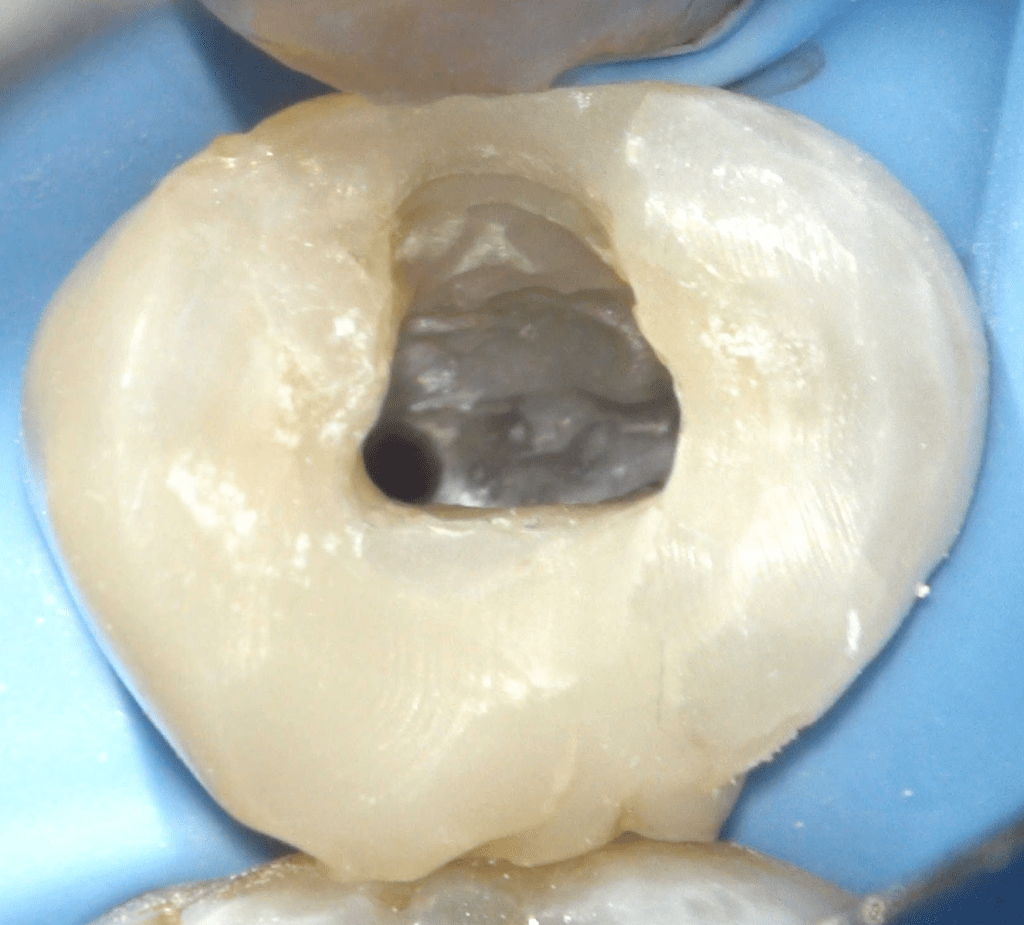

Reconstrucción preendodóntica

Molar superior